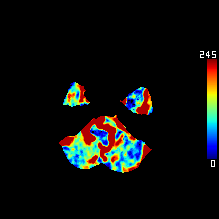

DeepClue-Precise CT 측부혈류영상

Perfusion CT를 이용한 측부혈류영상

동맥기

모세혈관기

조기정맥기

후기정맥기

지연기

조기정맥기까지 남은 허혈 영역 : 초기 뇌경색 영역과 일치 (일치율 0.97)

모세혈관기의 허혈 영역 : 허혈반음영을 반영 (일치율 0.89)